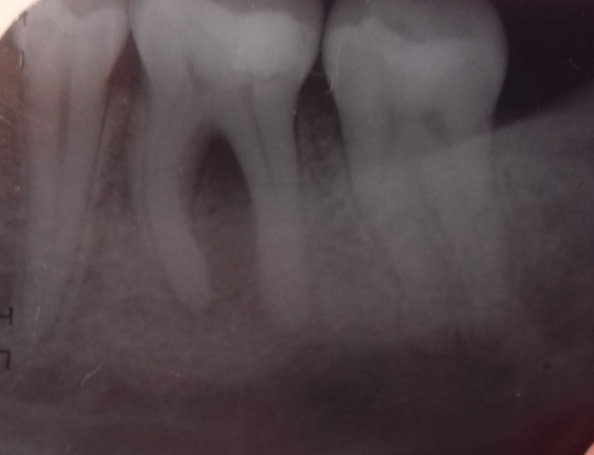

Здравствуйте. При принятии твердой и сладкой пищи, а также при ежедневной чистке зубов возникает ноющая боль в зубе (крайний левый на нижней челюсти). Стоматолог сказал, что есть небольшой кариес, поставили пломбу. Прошло уже три дня, а зуб всё равно ноет при накусывании. От чего это может быть и что делать в данной ситуации?

Добрый день . Скорее всего ваш стоматолог поставил неправильный диагноз или пломба завышает . Рекомендую обратиться на очный прием и после снимка вам все подробно расскажут. Не тяните , потеря времени может привести к потере зуба.